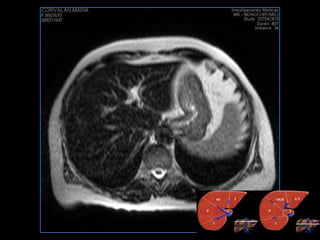

PROTOCOLO hígado graso AXIAL in phase y out phase AX T1 y AX fat sat +SAG T2  CON   GADOLINIO :  COR T1+AX T1(DIN) SAT: NO  FASE: RL THK: 4MM  COIL:  GAP: (FACTOR 1.4)  FOV: 40 CM NEX:2 SINCRONIZACION RESPIRATORIA EN 3 O 4 CICLOS ALE